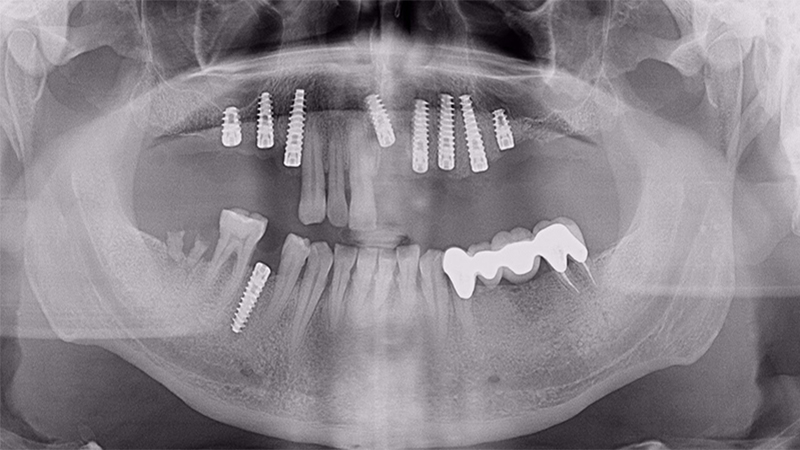

Implants

All on 4 Implants

All on 6 Implants

All on 8 Implants

FULL MOUTH REHABILITATION with IMPLANTS

Implant Patients